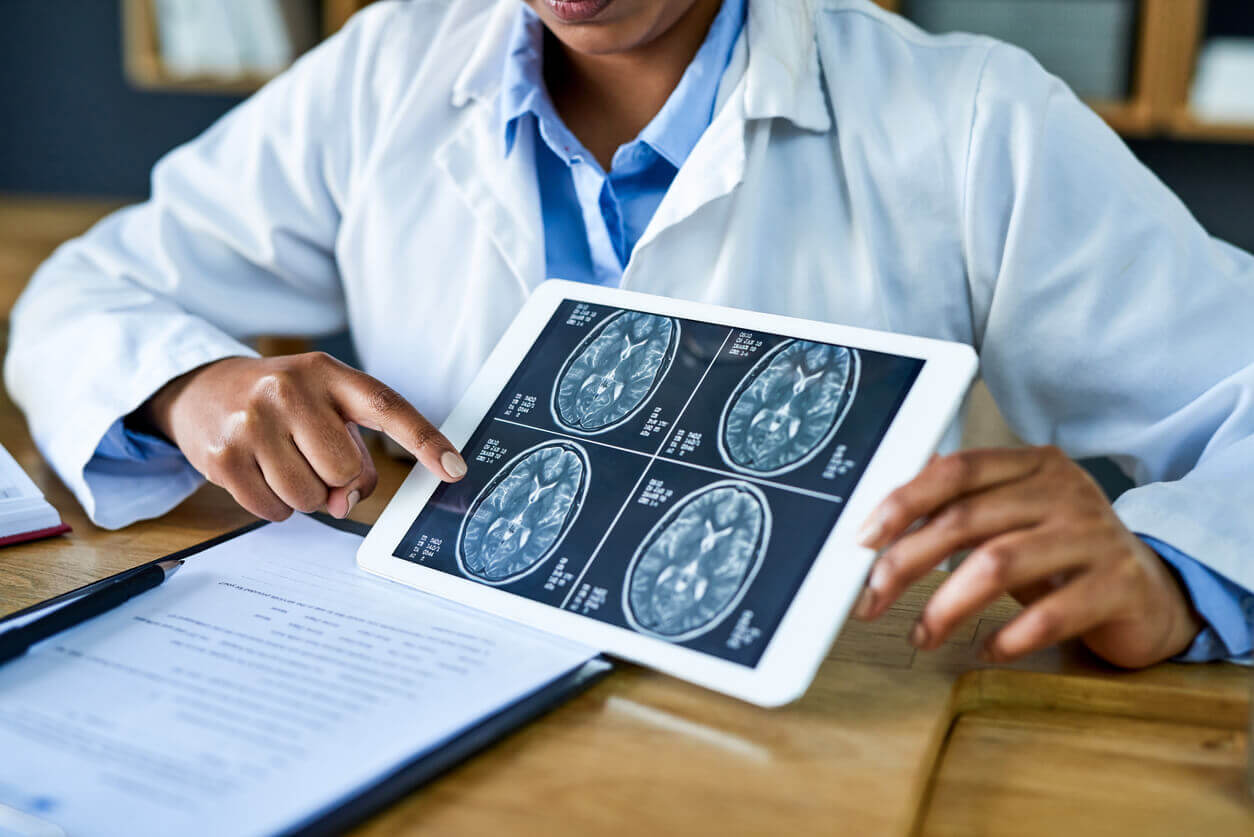

چه سردردهایی MRI میخواهند؟ راهنمای کامل تصمیمگیری

چه سردردهایی MRI میخواهند؟ راهنمای کامل تصمیمگیری یکی از پرتکرارترین سوالات بیماران این است: آیا لازم است برای سردردم MRI انجام دهم؟ واقعیت این است